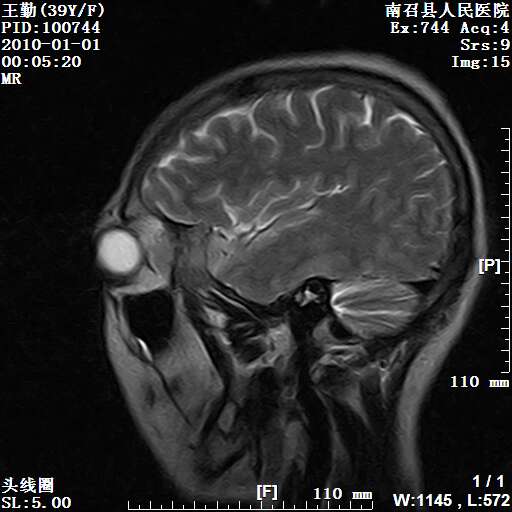

以下是引用随光逐影在2010-1-22 9:03:00的发言:[br]考虑左侧中颅窝(蝶骨翼区)脑膜瘤侵犯蝶骨翼并突入左侧眼眶。

以下是引用水过无痕在2010-1-22 14:55:00的发言:[br]一、定位:颅外占位;二、定性:恶性可能性大;三、组织来源:来源于左侧眼外直肌或其他部位;考虑为:横纹肌肉瘤>转移瘤>脑膜瘤.